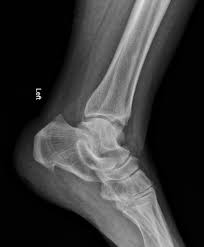

Haglund Deformity Radiology : Haglund Deformity Radiology Case Radiopaedia Org - Haglund's deformity is named after patrick haglund, who defined the condition in 1927.. This condition is often precipitated by wearing shoes with rigid backs that rub against the heel. Does haglund's deformity go away? Haglund deformity, also known as a pump bump , bauer bump, or mulholland deformity, is defined as bony enlargement formed at the posterosuperior aspect of the calcaneum. Haglund's deformity is characterized as an enlarged prominence of the superior aspect of the posterior calcaneus, which can cause painful inflammation within the retrocalcaneal bursa and anterior surface of the achilles tendon as a result of mechanical irritation. Insertional achilles tendinopathy retrocalcaneal bursitis haglund deformity (i.e.

Haglund deformity, also known as a pump bump , bauer bump, or mulholland deformity, is defined as bony enlargement formed at the posterosuperior aspect of the calcaneum.

Correct shoes that are supportive may prevent it. As associated problems such as heel bursitis settle, the size of the lump should reduce, but the bony why is it called haglunds deformity? Radiographic evaluation of haglund's deformity. The authors describe a new method of radiologic measurement of haglund's deformity, based on a radiologic study of 31 feet operated for posterior heel pain and more especially for calcaneal tendinopathies related to deformity of the calcaneus, and on a series of 60 asymptomatic feet. This deformity leads to retrocalcaneal bursitis. Haglund deformity, also known as a pump bump, bauer bump, or mulholland deformity, is defined as bony enlargement formed at the posterosuperior aspect of the calcaneum. Haglund's deformity is a bony enlargement at the level of the posterior part of the heel. The primary symptom of haglund's deformity is pain at the back of the heel. Haglund's deformity is named after patrick haglund, who defined the condition in 1927. There is a noticeable swelling on the back of heel also called bump. This includes home remedies and. Haglund's deformity is a bony enlargement on the back of the heel. Haglund's syndrome is a group of signs and symptoms consisting of haglund's deformity (which is an exostosis of the posterior calcaneal tuberosity) in combination with retrocalcaneal bursitis.

Does haglund's deformity go away? Other names for haglund's deformity include bauer bump, pump bump, or mulholland deformity, though it's most commonly known as haglund's heel. Haglund's deformity is characterized as an enlarged prominence of the superior aspect of the posterior calcaneus, which can cause painful inflammation within the retrocalcaneal bursa and anterior surface of the achilles tendon as a result of mechanical irritation. When this bony enlargement rubs against the achilles tendon and overlying bursa, inflammation of the retrocalcaneal bursa occurs. The soft tissues present at the back of your heel become irritated due to the rubbing of the extra bony growth.

The presence of a haglund's deformity narrows this space considerbly thereby casuing or exacerbating problems such as retrocalcaneal bursitis. When this bony enlargement rubs against the achilles tendon and overlying bursa, inflammation of the retrocalcaneal bursa occurs. Does haglund's deformity go away? Haglund's deformity, also called pump bump, winter heel, mulholland deformity, or retrocalcaneal exostosis, is a bony enlargement of the posterosuperior heel bone, called the calcaneus, at the insertion site of the haglund syndrome: The soft tissue near the achilles tendon becomes irritated when the bony enlargement rubs against shoes.